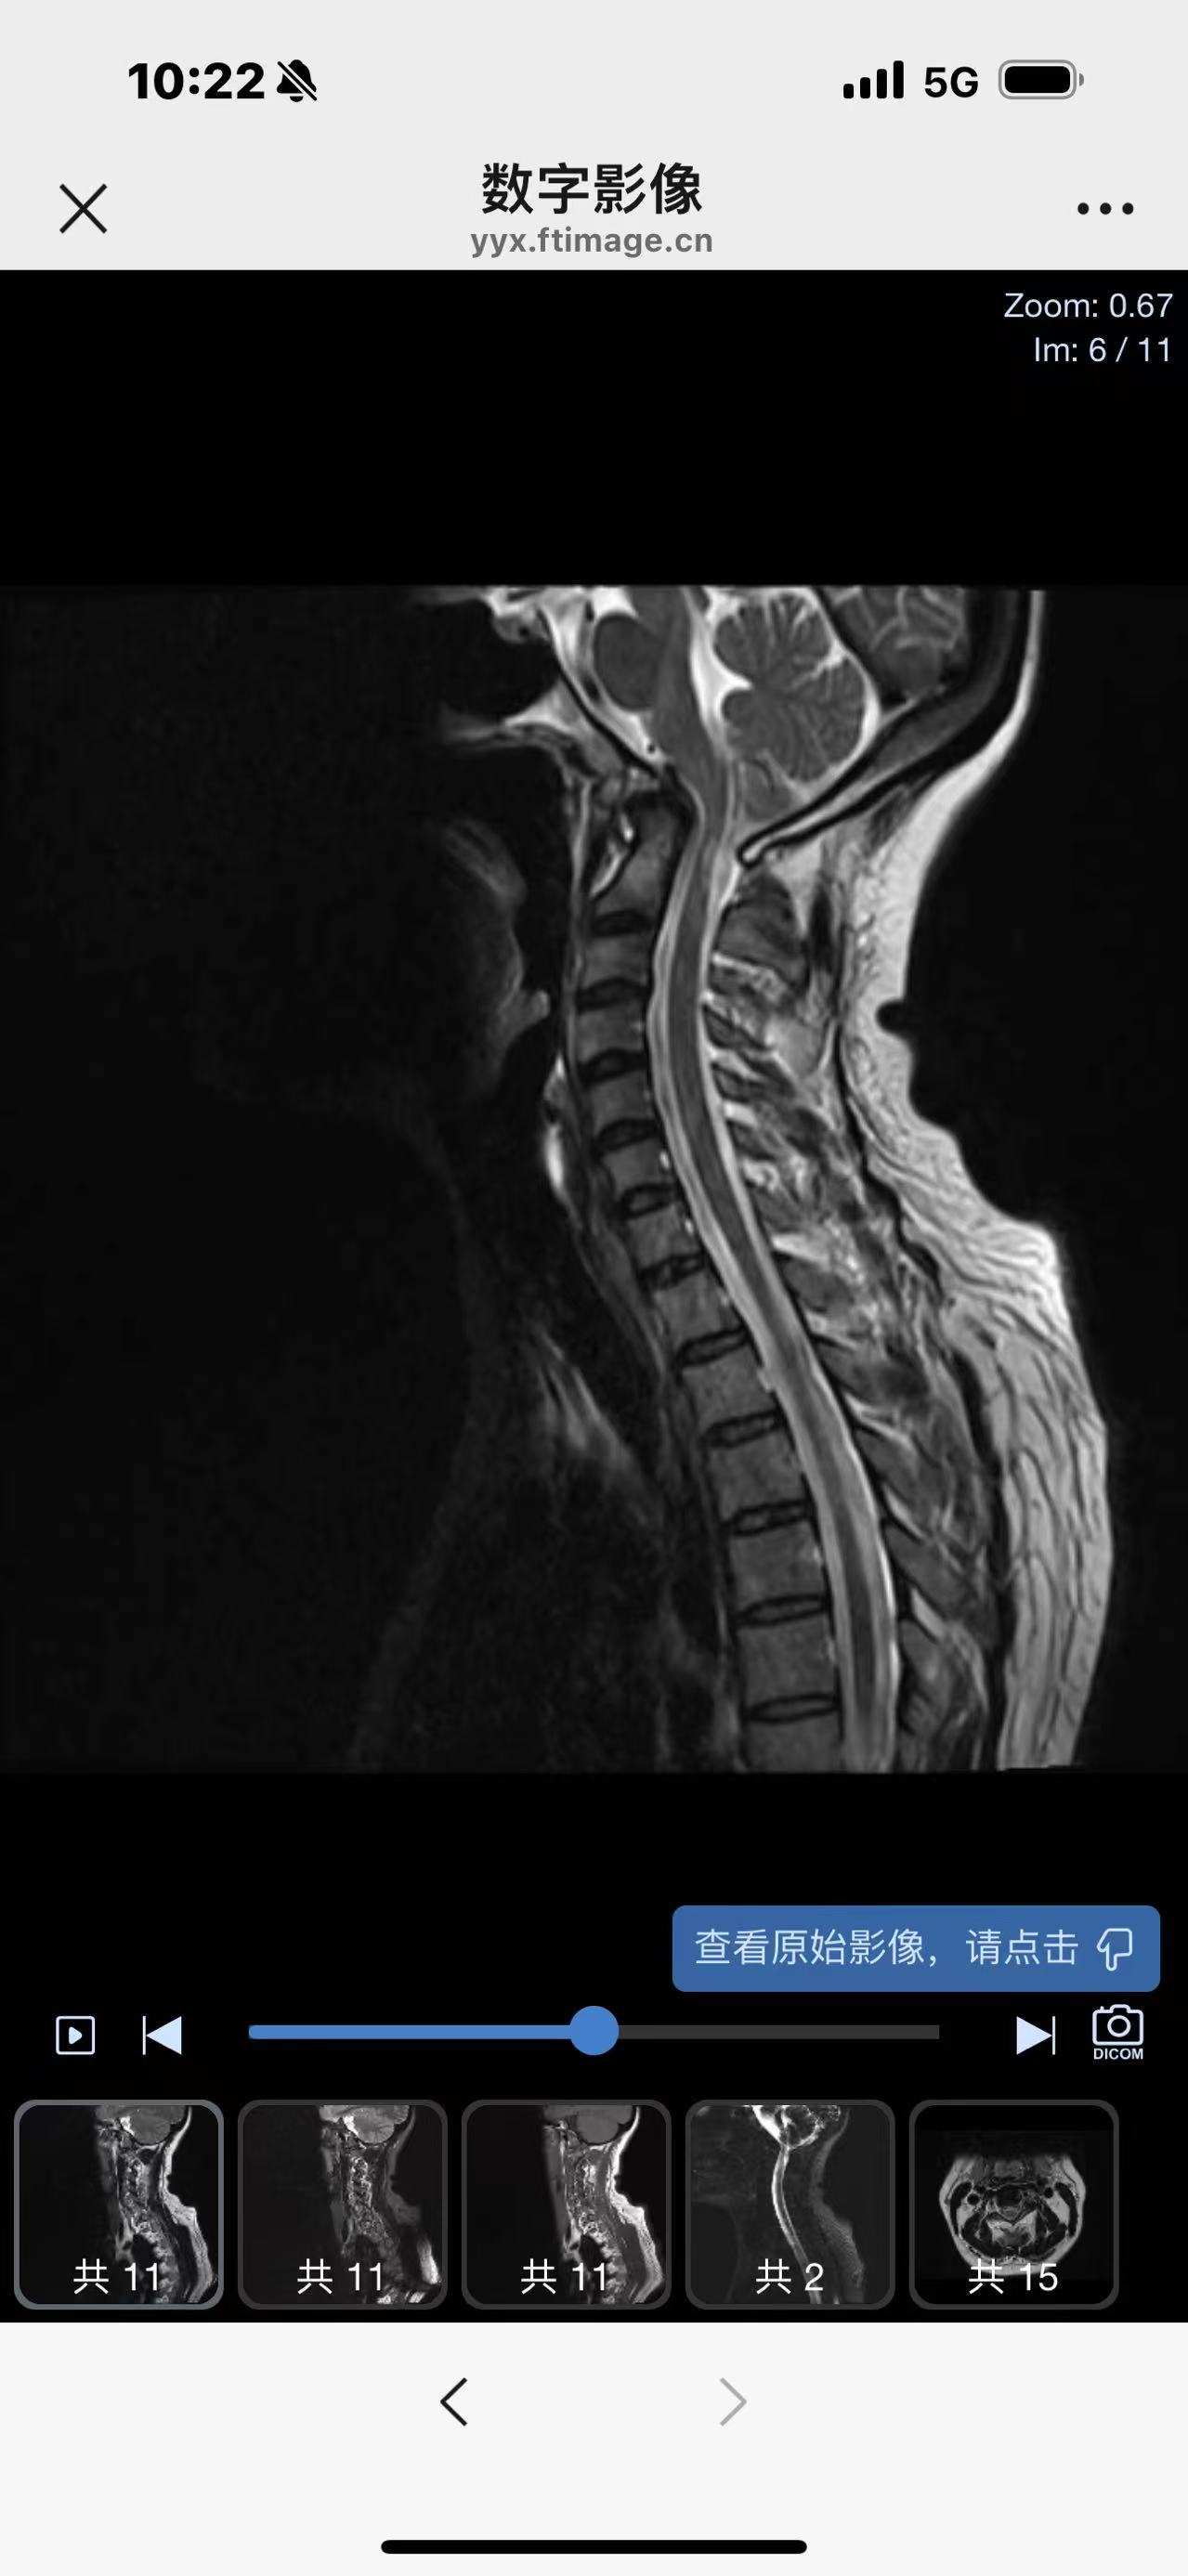

• 诊断:寰枢椎脱位

• 影像:

• 术后影像: